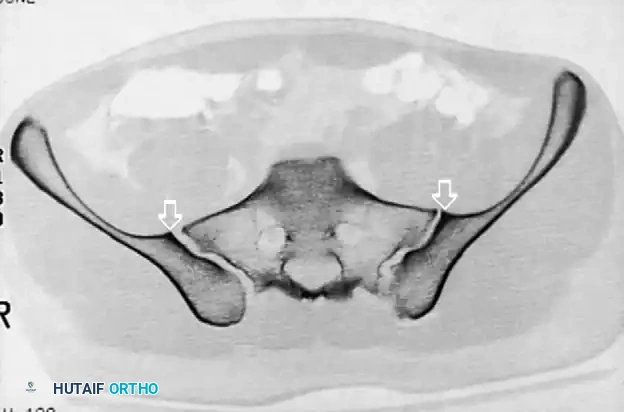

Inlet pelvic radiograph demonstrating correct anterior-posterior trajectory of the guide wires and screws.

Image

Alternative inlet view confirming intraosseous placement of bilateral iliosacral screws.

• Switch to Outlet View: Confirm the wire is superior to the S1 neuroforamen and inferior to the S1 superior endplate.

Outlet pelvic radiograph confirming screws are safely positioned above the S1 neural foramina.